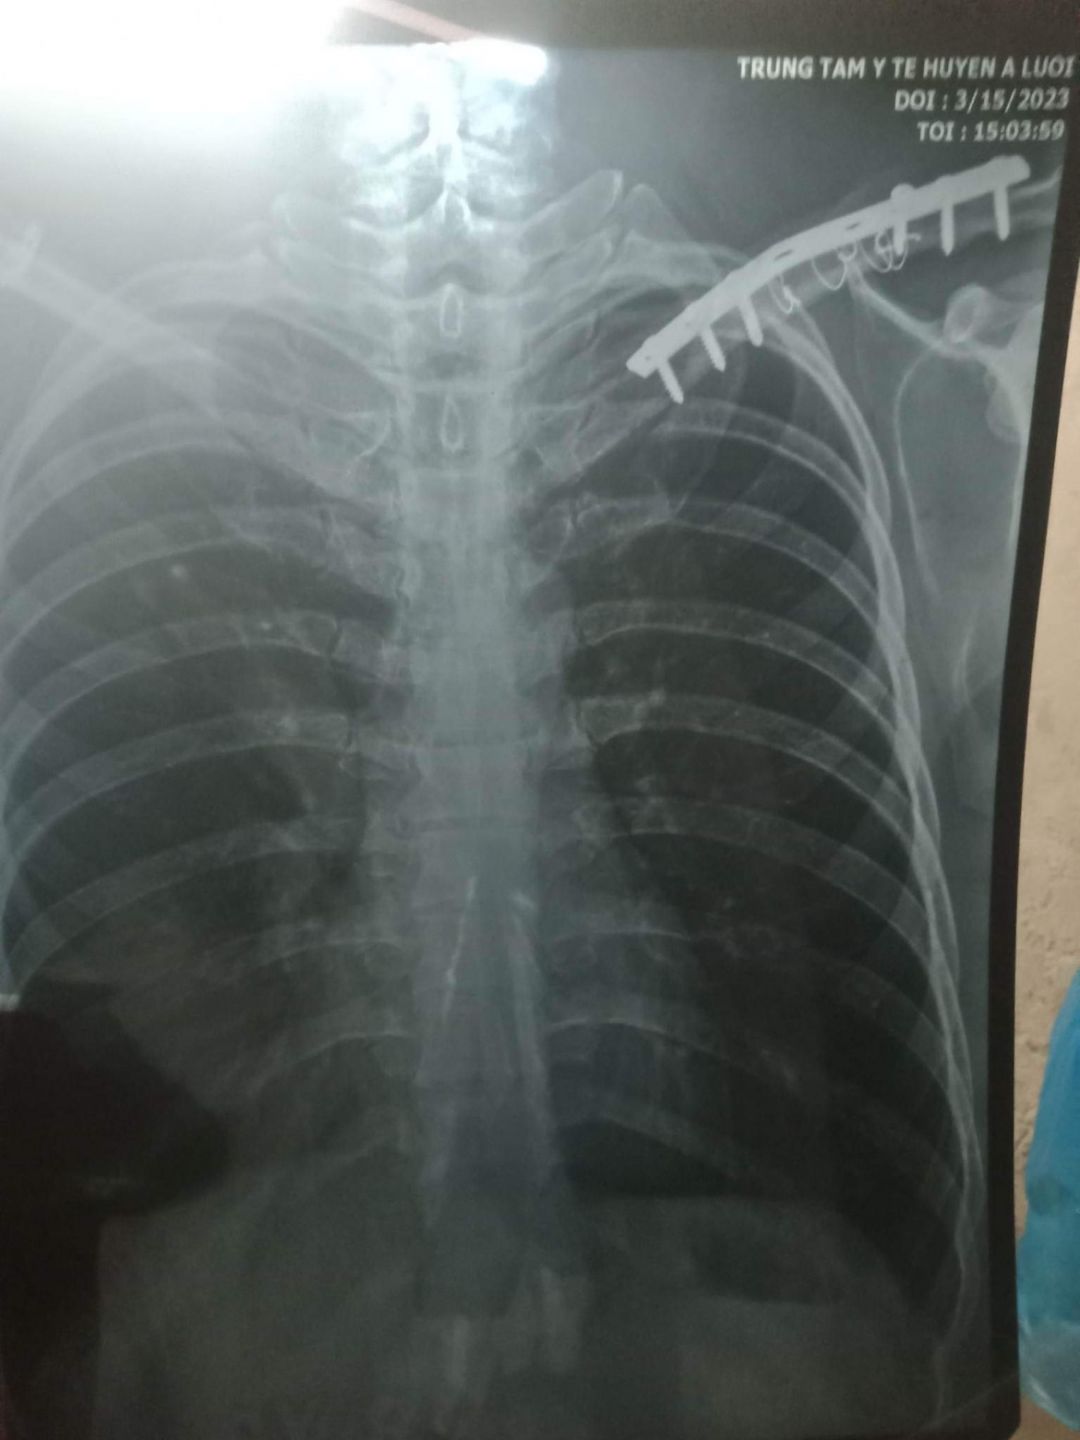

3. Hồ sơ chụp phim có ạ ( em up đính kèm ảnh ạ

4. Giảm khi tháo ốc vít: Khó báo số tiền chính xác ạ, thường thì thuốc ngoài bhyt chi phí nhiều , phí mổ cũng nằm ngoài bhyt ạ. Ra viện thì được thanh toán gần 45 nghìn đồng/1 ngày nhưng hiện không biết nếu mổ thì nằm bao nhiêu ngày ạ( em có up ảnh sdt khoa chấn thương

Em xin thông tin hoàn cảnh của HS Nguyễn Thị Thu Hương. Bố và mẹ em ly hôn từ năm 2019, bố tên là Nguyễn Văn Dũng 38 tuổi. Nghề nghiệp tự do. Thu nhập trung bình một tháng từ 1.5 đến 2 triệu, phụ thuộc vào thời tiết và sức khoẻ. Một mình bố nuôi hai con đang ăn học. Con gái đầu tên là Nguyễn Thị Thu Hương 18 tuổi đang học lớp 12. Con gái thứ hai tên là Nguyễn Hoài Thu Hà, 15 tuổi đang học lớp 10. Gia đình là hộ nghèo. Năm 2019 anh Dũng bị tai nạn xe máy khi đi làm về. Anh bị gãy ở bả vai phải lắp 6 ốc vít, trời trở lạnh anh lại đau nhức xương không làm gì đc. Bác sĩ dặn nếu có kinh phí thì từ 1 đến 2 năm phải nhập viện để tháo ốc vít với kính phí khoảng 20 triệu đồng. Số tiền quá lớn nên 5 năm rồi chưa tháo vít được ở tay, điều này ảnh hưởng đến sức khoẻ dẫn đến sức khoẻ anh không ổn định để lao động nuôi các con

Anh không có tiền, vì anh là thu nhập chính của gia đình, nay lại đau ốm không làm thêm kiếm tiền được, cả 3 cha con hiện tại đang xin ăn ở nhà ông bà nội. Nhà có bóng đèn mà nay lại bị cháy, anh cũng không có tiền để mua cái mới để thắp sáng. Kính mong quý mạnh thường quân xem xét và giúp đỡ hoàn cảnh của em Nguyễn Thị Thu Hương.